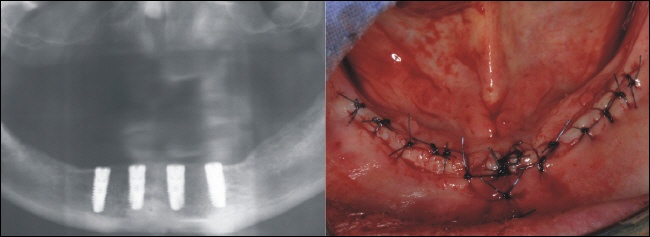

Freilegung

||